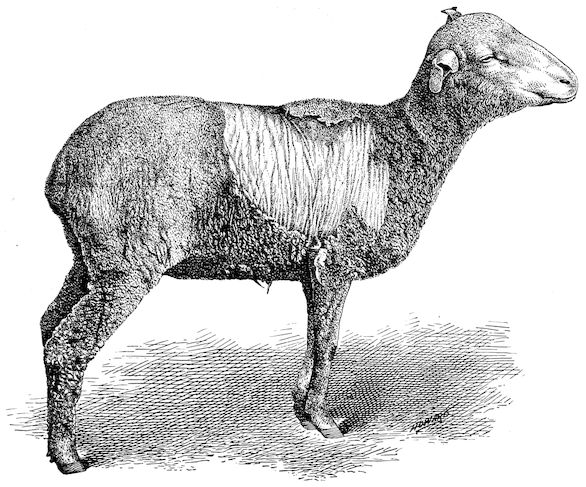

In the adult, the development of the horns varies with different breeds and is affected by sex. In the bull the horns are short, but in the cow and ox long. Short and fine in animals of improved breed like the Durham, they are long and thick in breeds of working oxen.